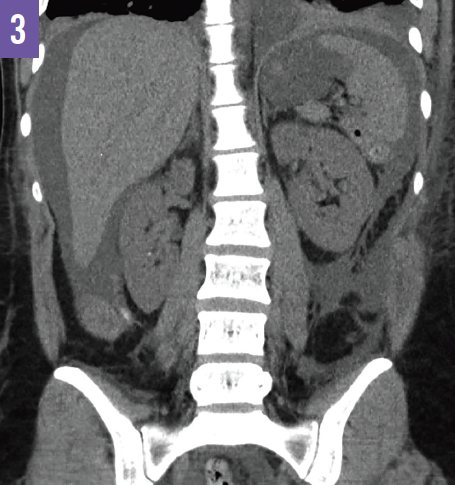

A urinary catheter was placed, resulting in the immediate return of 200 mL of clear fluid; however, over the next 2 hours, urine output was 1300 mL. Computed tomography (CT) of the abdomen and pelvis revealed protrusion of the urinary catheter through the dome of the bladder into the intraperitoneal space, large ascites, and free intraperitoneal air (Figures 1 and 2). The liver and kidneys appeared normal; there was no hydronephrosis (Figure 3).

Figure 3: CT of the abdomen and pelvis demonstrating ascites and normal kidneys without evidence of hydronephrosis.